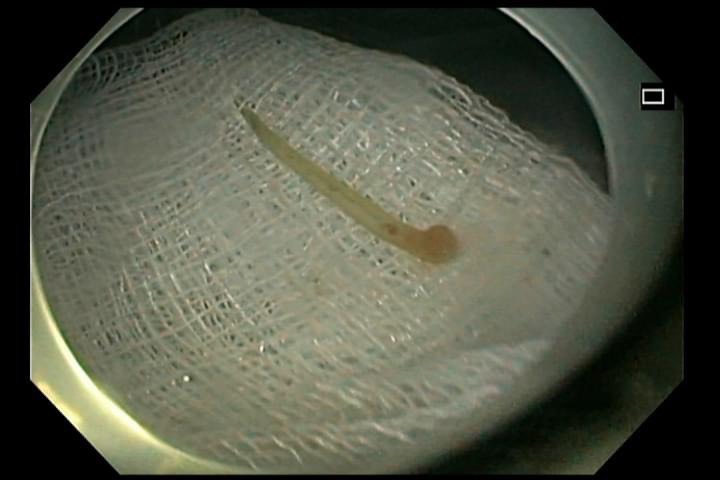

Tại đây, bệnh nhân được các bác sĩ nội soi thực quản phát hiện có dị vật hình dạng xương cá ở 1/3 trên thực quản, vị trí tổn thương đã có hiện tượng phù nề, hóa mủ nhưng rất may xương cá chưa đâm thủng hoàn toàn thực quản. Các bác sĩ đã tiến hành nội soi gắp dị vật xương cá có kích thước dài gần 3cm ra ngoài cho bệnh nhân.

Hình ảnh dị vật xương cá được gắp ra khỏi thực quản của bệnh nhân